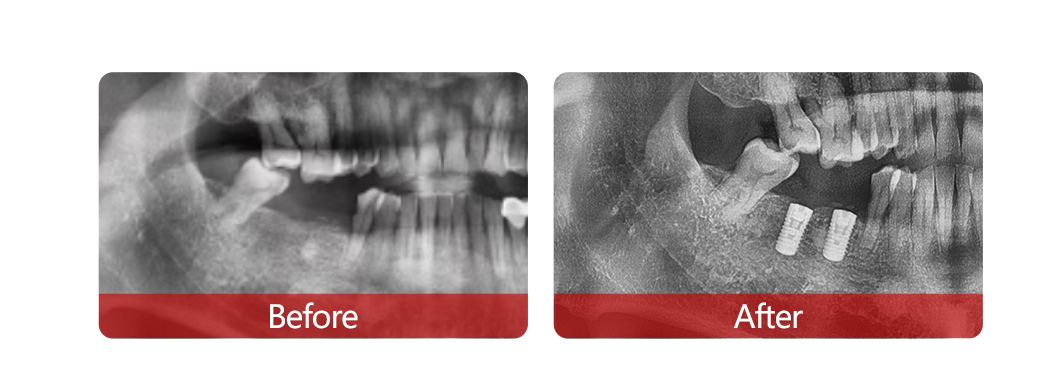

【新桥快讯】植树节|数字化种植直播!60岁大叔20分钟喜获2颗新牙

活动现场,近百名缺牙市民和成都电视台等媒体一道,零距离“围观”60岁的鲍叔叔仅用20分钟落齿重生2颗新牙的全过程,植树节当日“种牙得牙”的梦想成真。